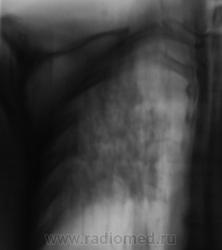

Людмила Григолрьевна, но тут, то процесс двусторонний, хоть преимущественно правосторонний. А на полноформатных изображениях (томограммах), и очаги справа в среднем и нижнем легочных полях дифференцировались.

Вот, и мы так решили, с учетов ограничеснных возможностей нашей ЦРБ-ушки. Взял коллега фтизиатр "изображения", а также и изображения в динамике, а также необходимый "гарнир", и поехал в головное "фтизное" учреждение. В учреждении проконсультировали и выставили правосторонний инфильтративный. Ну и у нас считай - гора с плеч...

Пациента госпитализировали в областное противотуберкулёзное учреждение. Пролечили в течение месяца.... и выписали.

Произведен контроль после лечения. Заключение рентгенолога данного учреждения - "Со стороны органов грудной полости патологических изменений не выявлено".